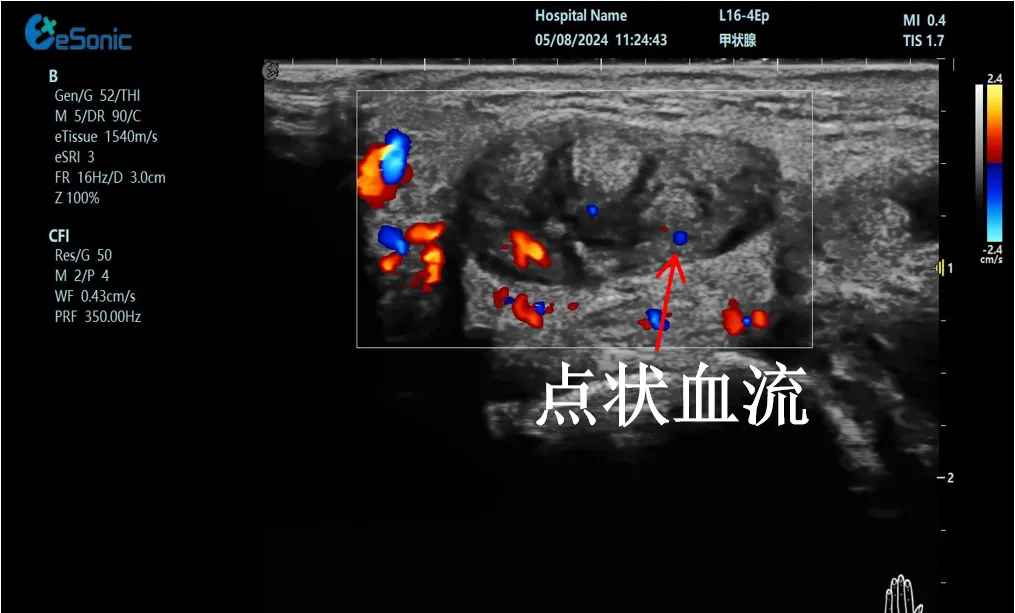

mFlow?技术在腱鞘炎诊疗中的应用

【背景】:左手腕关节第四腔室腱鞘炎。

【痛点】:普通彩色多普勒不敏感,只能看到细小点状血流,容易被忽略,难以进行分级诊断和疗效评估。

【方案】:百乐博平台医疗(ESI)超微血流技术可以看到腔室内肌腱周围环状血流,可充分提示:

1、处于炎症活动期;

2、根据血流进行分级诊断提示1级;

3、治疗后根据血流多少评估疗效(见右下图:治疗10天后复查超声,微血流图像血供消失)。